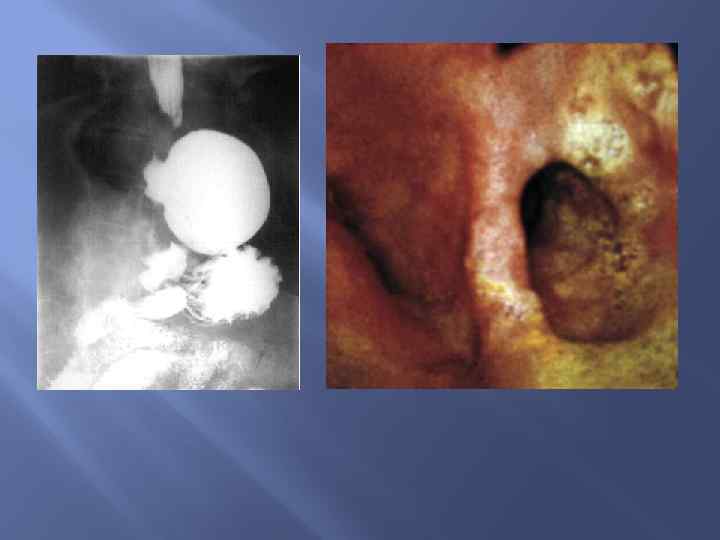

Дивертикулы пищевода

Дивертикулы пищевода